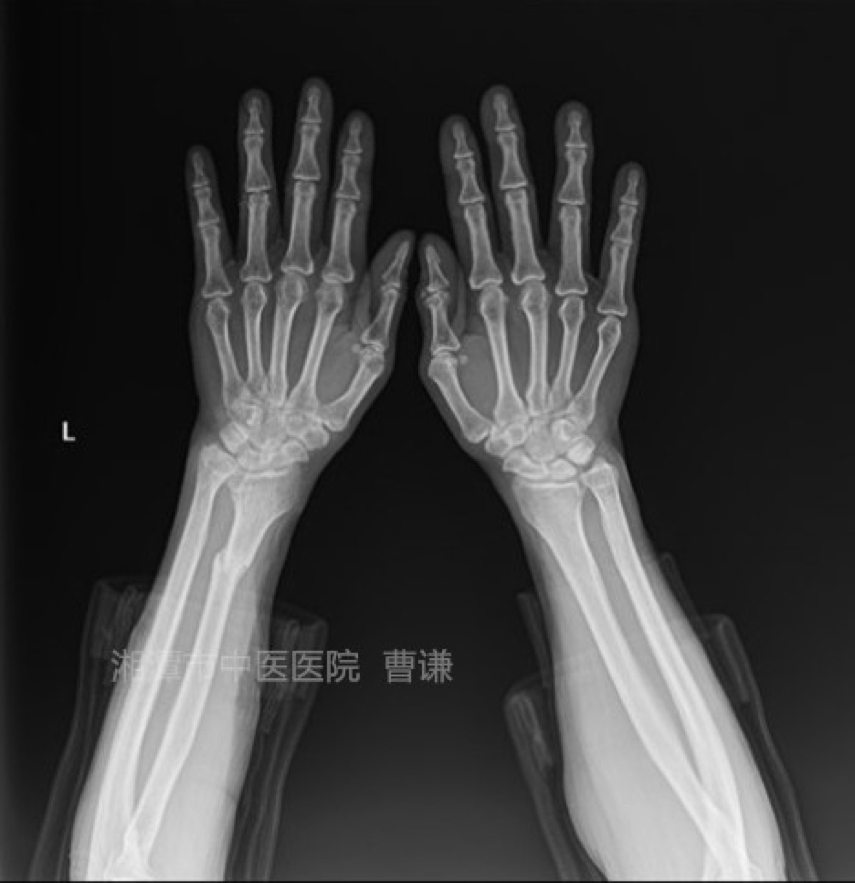

患者外伤后拍片示:右桡骨中下段骨折,下尺桡关节分离。

患者在诊所治疗20天后拍片复查示:下尺桡关节仍有分离。

伤后21天患者就诊于我院,采用手法复位,小夹板外固定,拍片复查示下尺桡关节分离已纠正。